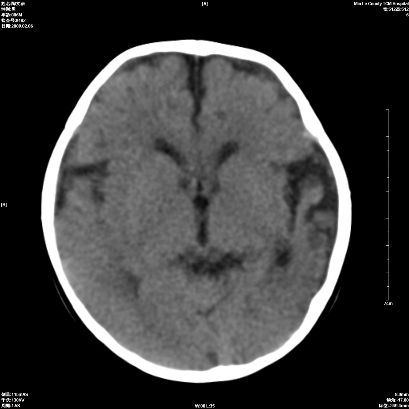

以下是引用wxq2008在2009-2-6 17:01:00的发言:[br]hie后遗症脑萎缩。

以下是引用学医在2009-2-6 21:45:00的发言:[br]hie后遗改变